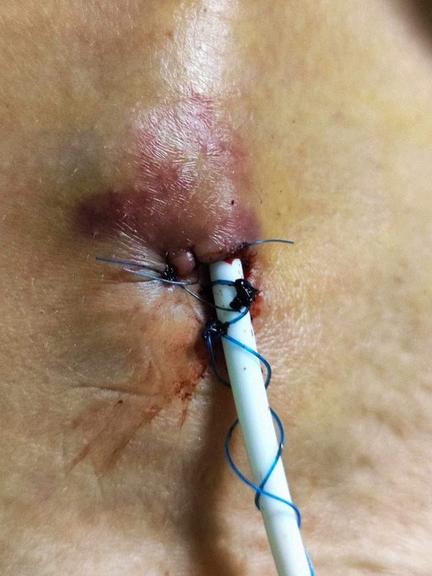

W związku z koniecznością podawania dożylnego antybiotyków, płynów infuzyjnych oraz żywienia pozajelitowego zdecydowano o założeniu pośredniego dostępu naczyniowego typu Midline.

Odstąpiono od założenia wkłucia centralnego PICC z powodu planowanego założenia cewnika tunelizowanego typu Broviac oraz zakrzepicę w obrębie naczyń centralnych, a także zwiększone ryzyko zatorowości. W badaniu USG zlokalizowano lewą żyłę odłokciową o średnicy 5 mm, podskórnie znieczulono miejsce wkłucia i metodą Seldingera wprowadzono cewnik Midline 4Fr/20 cm, uzyskując swobodny wypływ krwi. Cewnik zabezpieczono systemem GripLock oraz opatrunkiem transparentnym. Cewnik utrzymano przez 9 tygodni i 1 dzień, stosując regularną, zgodną z procedurą zmianę opatrunków Wkłucie nie wykazywało cech niedrożności, wynaczynienia ani wysunięcia. Skóra wokół wkłucia była wolna od objawów infekcji i stanu zapalnego. Pacjentka nie odczuwała dyskomfortu związanego z użytkowaniem wkłucia pośredniego.